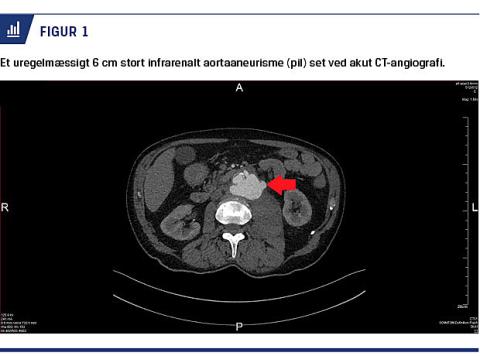

senere blev der dyrket M. bovis-BCG. Behandlingen blev indledt med rifampicin, isoniazid, ethambutol, moxifloxacin og pyridoxin. Patientens almentilstand forbedredes initialt, men på grund af vedvarende træthed og appetitløshed blev der i april 2017 foretaget en ny PET-CT, som viste patologisk øget metabolisme i de mediastinale og retroperitoneale lymfeknuder. Under et forsøg på at bioptere lymfeknuderne en uge senere begyndte han at bløde i psoasmuskulaturen. En akut CT-angiografi viste et 6 cm bredt, uregelmæssigt infrarenalt AA, som var rumperet (Figur 1). Han blev opereret akut med resektion af det inficerede væv. Aorta blev rekonstrueret med en autolog graft, der var tildannet af patientens egen vena femoralis, som duplikeredes til en længde på 8 cm og en diameter på 2 cm. Operationstiden var fire en halv time, og blodtabet var 1.600 ml. Det postoperative forløb var ukompliceret, og patienten blev efter seks dage tilbageflyttet til den infektionsmedicinske afdeling til fortsat antituberkuløs behandling. Histologi af aorta abdominalis viste nekrotiserende, granulomatøs inflammation, men ved Ziehl-Neelsen-farvning kunne der ikke påvises syrefaste stave. Dyrkning af aortavæg var negativ. Den antituberkuløse terapi fortsatte i ni måneder, og patientens almentilstand blev gradvis forbedret.